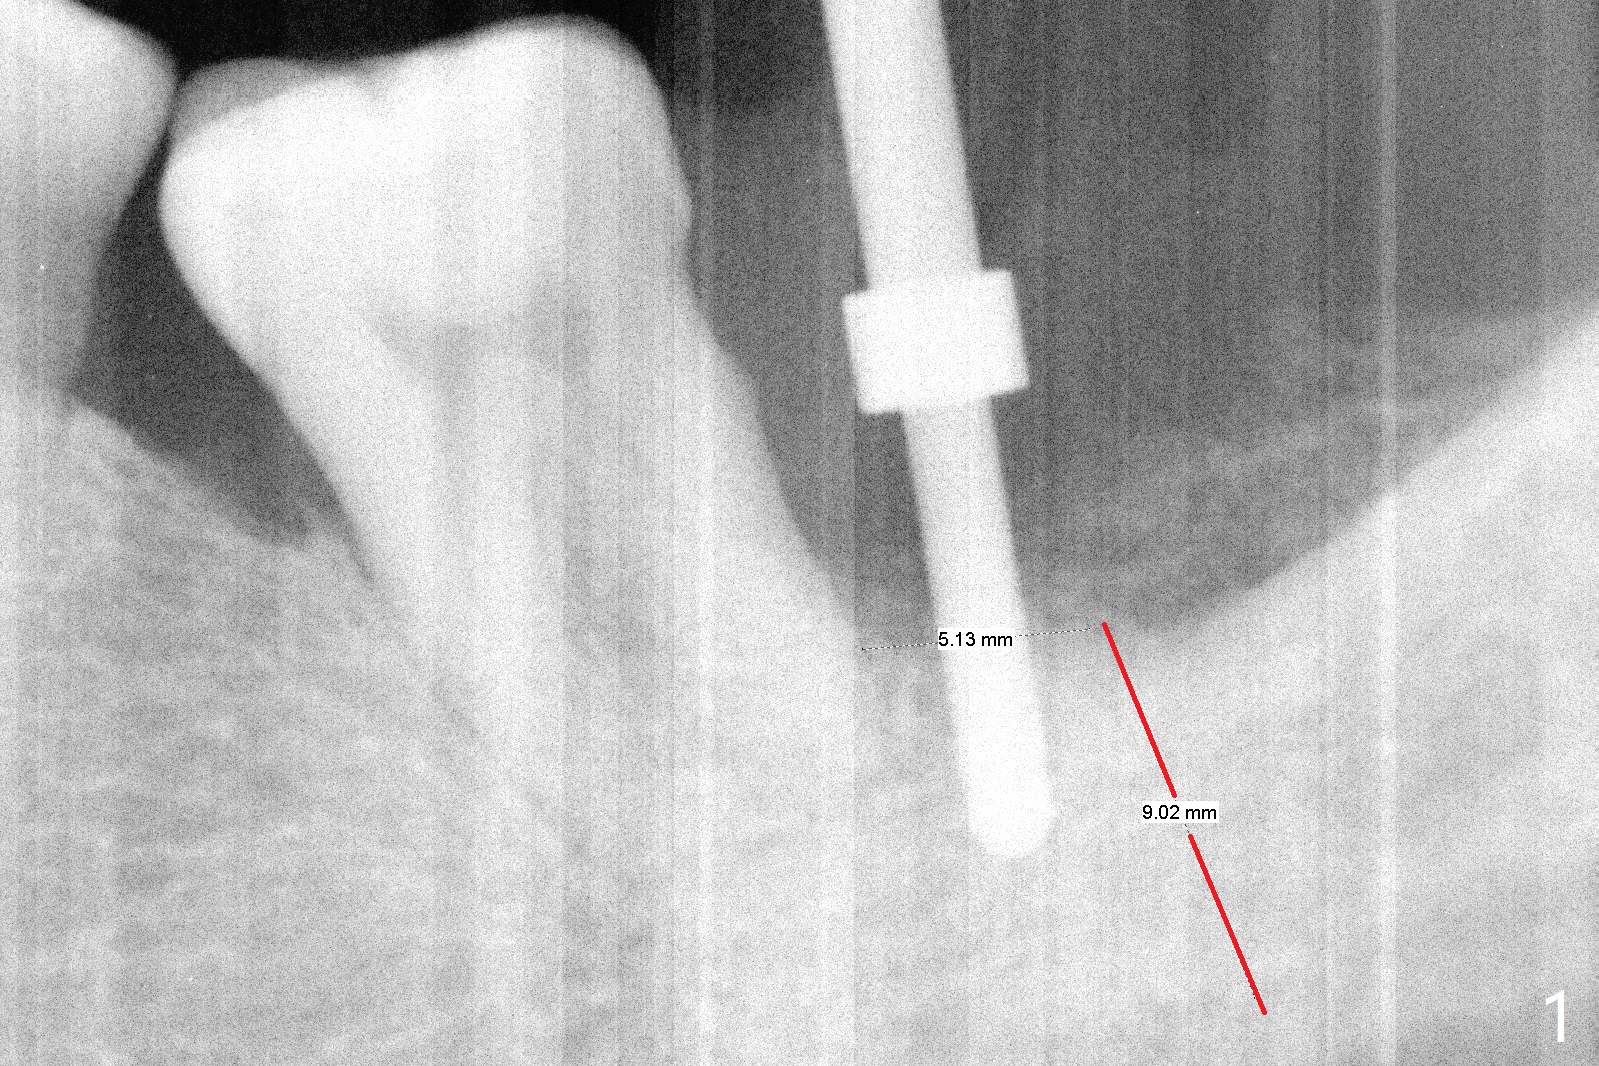

After extraction, curettage and Clindamycine gauzes in the sockets of the tooth #18 for 3 times, a 2 mm pilot drill makes initial osteotomy in the socket from 8 to 14 mm (Fig.1 (gingival level)). It appears that the osteotomy should move distal (Fig.1: red line, Fig.2 (17 mm)). After 5.9x10 mm drill, a 5.9 mm tap is placed (Fig.3). There is 4 mm clearance. Following 6.4x10 mm drill for 2 mm deeper, a 6.4x10 mm implant is placed with 60 Ncm. The implant plateau is level with the lingual crest, while the mesiobuccodistal bone is low. Autogenous bone mixed with Osteogen is placed in the defect area, followed by insertion of a 6.8x4(4) mm abutment (Fig.5). Collagen dressing is placed on the top of the graft. An immediate provisional is fabricated to close the remaining socket. Impression is taken 7 months postop (Fig.6). There seems to be no bone loss 23 months post cementation without opposing teeth (Fig.7) in spite of severe periodontitis at #19 (Fig.8 (25 months post cementation)). More surprising is the asymptomatic lingual (L) plate perforation, revealed by CT (Fig.9 arrowheads).